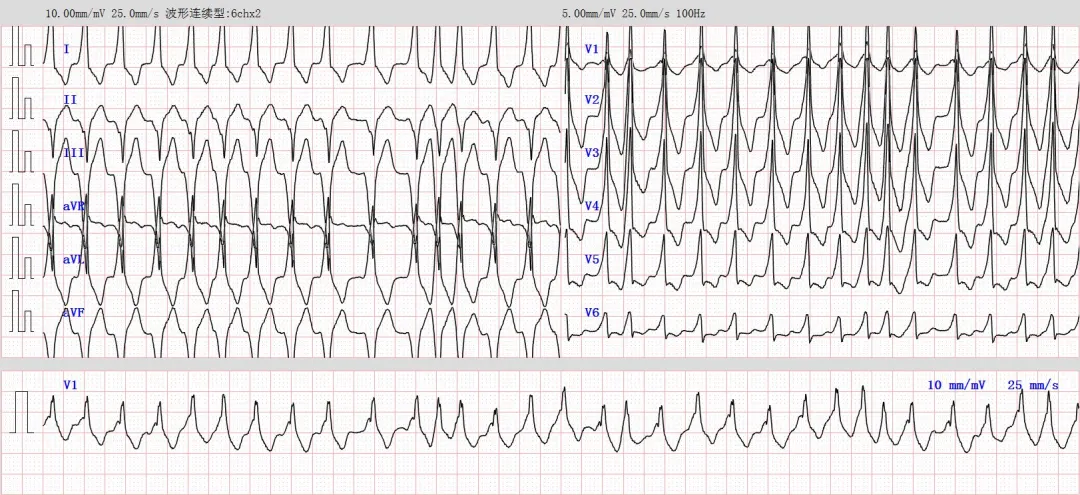

例如这一些:

图1与图2均来自同行老师供图。

上述两图均符合①QRS波宽大畸形+②RR间期绝对不齐,这两个特点,所以我个人的考虑是房颤伴预激。

QRS波的宽大畸形,可以用预激时QRS波起始部宽顿,且QRS波轻度增宽,可继发引起ST-T改变。而RR间期绝对不齐,就属于房颤的特点。

返回看图1与图2,QRS波宽大畸形,属于显性预激,应当为房室旁道前传优势型。且V1-V2导联R波/预激波向上,属于A型预激,推测房室旁道位于左侧。